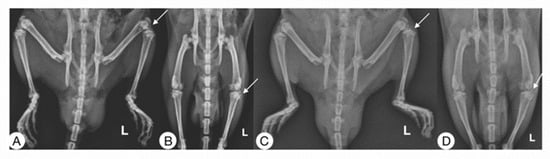

Radiographic studies of the rats (Figure 4) were performed at 0, 7, and 14 days post-surgery, corresponding to the periods before surgical induction of OA, treatment administration, and sacrifice, respectively.

On day 0, none of the animals showed any lesions, and all received a score of “0” on the Kellgren and Lawrence scale [23]. After surgical induction of OA on day 7, the rats showed radiographic changes in the knee with ACLT that consisted of irregularities on the articular surface, osteophytes, and changes in density suggestive of sclerosis. All with an average score of “2” compared to the contralateral knees are considered controls in which no differences were observed.

In the radiographic evaluation on day 14, the ACLT groups showed more severe radiographic changes, with scores of 2 to 3.5 according to the scale of Kellgren and Lawrence [23] (Figure 5). Significant differences were found in the animals treated with Np-Q, while the animals treated with HA were the ones that best preserved the bone structure between the knees with ACLT. Although there were significant differences between those treated with Np-Q and AH, they did not show significant differences compared to the other treatments with ACLT.

The rats treated with Np-GSH showed slightly non-significant changes compared to those treated with AH and Hartmann solution (p ≤ 0.001). Significant radiographic changes were observed in the control knees after administration of the different treatments. Animals treated with Hartmann solution, acetic acid, and HA did not show radiographic changes (Figure 5).

Figure 4. Radiographic images (mediolateral and anteroposterior) of rats 14 days post-surgery are shown. Right pelvic limb control and left ACLT. (A,B) Rat treated with Hartmann solution. (C,D) Rat treated with Np-GSH. The arrows show where the transection was carried out in each case.